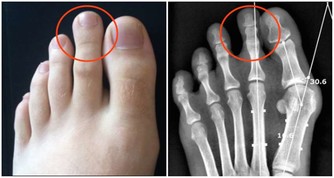

3. 排便時用力過猛

因為種種原因,許多人在排便時用勁過猛;如此便會對肛門周圍的血管造成很大壓力,嚴重時會導致血管破裂,廁紙上會有明顯的血跡;長此以往很有可能誘發痔瘡。建議在排便時不要太過用勁,無法排出時,可以輕揉腹部,或是通過調整飲食習慣來促進消化道健康。